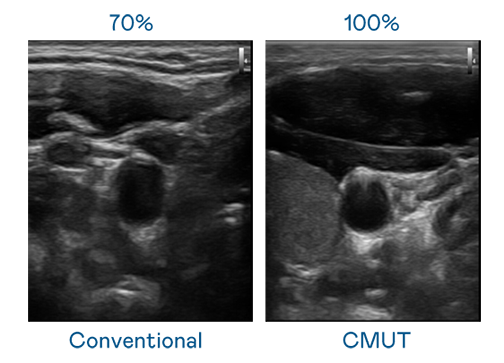

CMUT 技术是一种用电容式微机电元件来产生超音波讯号的技术。与传统 PZT 压电式技术相比,CMUT 频宽增加 30%,更宽频的超音波讯号让影像解析度大幅提升,是实现高影像品质医疗超音波扫描、促进精准医疗发展的关键技术。

大频宽带来超清晰影像

超音波影像的解析度高低,首先取决于探头能发出的讯号频宽。非凡游戏 CMUT 可提供高清晰的超音波讯号,提供高频宽、高灵敏度、影像纹理细节更高的超音波影像,协助医护人员缩短影像判读时间及利用精准的医疗影像进行诊断。